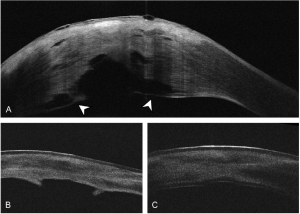

- Anterior Segment Optical Coherence Tomography (AS-OCT): AS-OCT can be used to diagnose ACH as it allows for visualization of the rupture in DM or posterior stroma, and the extent of detachment from the cornea. Additionally, it can be used to monitor the clinical course, including resolution of edema, reattachment of DM, the absence of DM, and scar formation.[15]

A. AS-OCT of the cornea at 10 days after presentation showing reattachment of DM. Shadowing from the stromal obscures part of the posterior cornea edema. In the visualized portion of the posterior cornea, a water cleft separates a thin layer of posterior stroma and DM from the remaining stroma (arrowheads). B. AS-OCT 5 weeks after presentation demonstrates improving corneal edema with persistent haze, an irregular contour of the central posterior cornea, and protrusions of tissue. The contour of the central posterior cornea is irregular. C. AS-OCT 1 week after ultrathin DSAEK shows a well-attached graft.[14] - In-vivo confocal microscopy (IVCM): IVCM, which evaluates tissue at a cellular level, can demonstrate epithelial and stromal edema, which appears as prominent epithelial cell borders and areas of hyper-reflectivity surrounding stromal keratocytes.[16] IVCM can also be used to detect inflammatory cells in the cornea. The presence of these cells longer than 4 weeks is associated with the development of corneal neovascularization.[17]